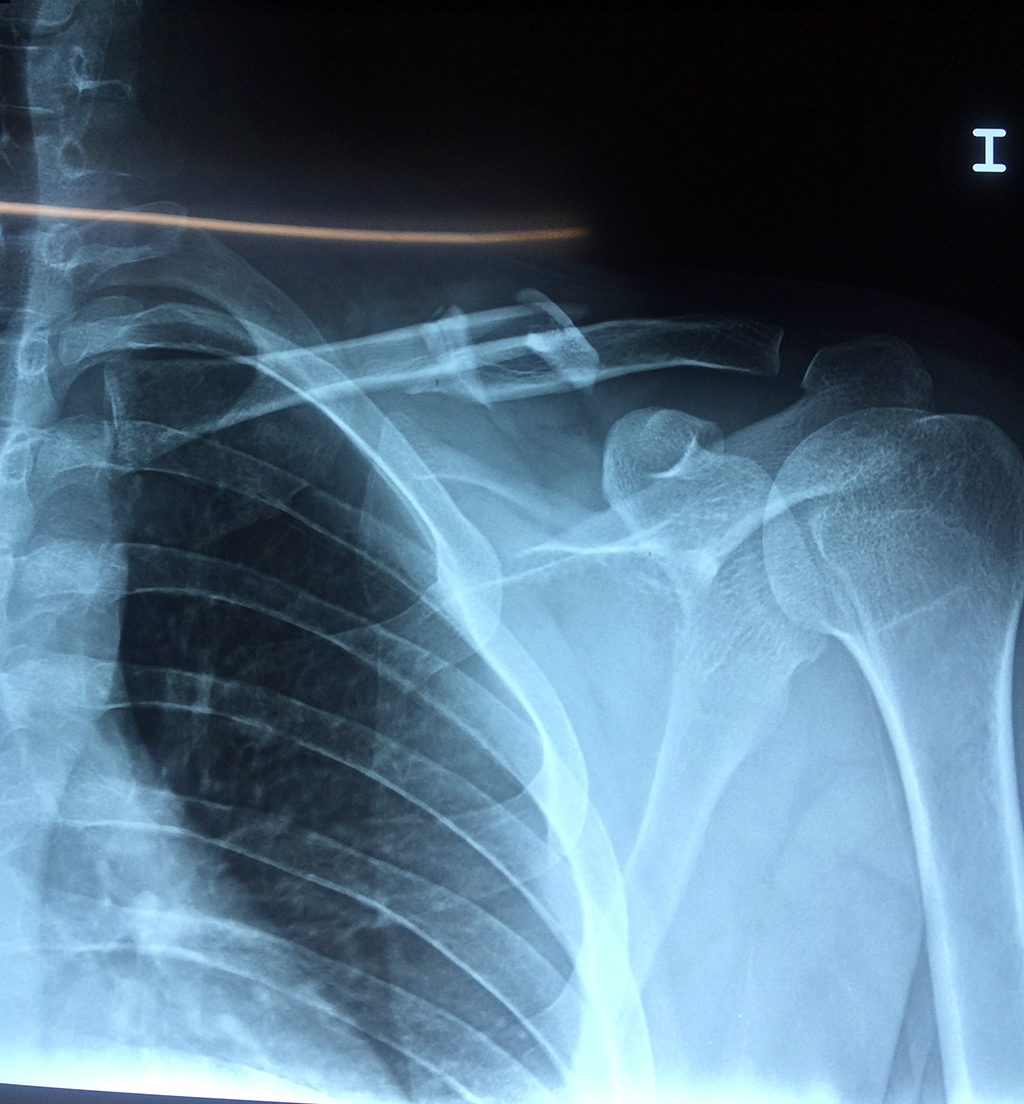

Cirugías de Húmero - Clavícula

La clavícula es un hueso largo, con forma de "S" itálica, situado en la parte anterosuperior del tórax. Junto con la escápula forman la cintura escapular. Se puede palpar por toda su longitud y se extiende del esternón al acromion de la escápula, siguiendo una dirección oblicua lateral y posterior.

Se considera el único medio de unión entre el miembro superior y el tórax. A pesar de su aspecto, similar al de un hueso largo, posee una estructura semejante a la de un hueso plano, ya que carece de epífisis y de diáfisis, lo que la harían entrar dentro de la clasificación de hueso largo. Carece de un canal medular propiamente dicho.